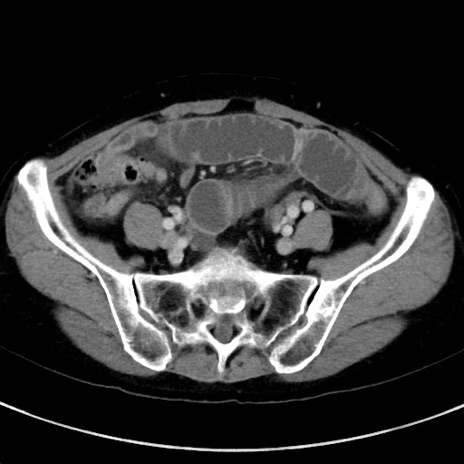

冠状断像

【症例】70歳代女性

【主訴】下腹部痛・嘔吐

【現病歴】2日前より腹痛あり。昨日嘔吐あり。症状改善しないため来院。

【既往歴】胃GISTに対して胃部分切除後。

【身体所見】BT 37.1℃、BP 128/77mmHg、腹部:平坦・軟、下腹部に圧痛あり。

【データ】WBC 10200、CRP 0.31